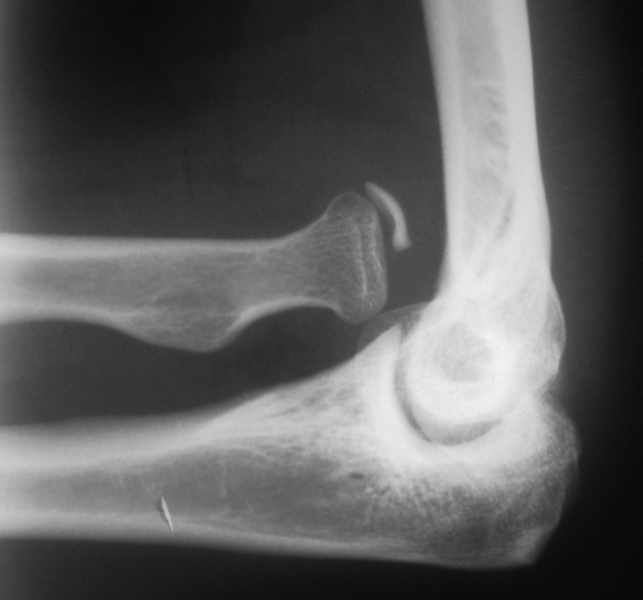

Мужчина 28 лет. Поступил в отделение по поводу застарелого вывиха левой лучевой кости. Со

слов больного, травму получил в 2001 году (предположительно переломовывих Монтеджи). 4

месяца назад начало беспокоить онемение в левой руке, от кончиков пальцев до верхней трети

левого предплечья, по утрам. После разминки эспандером онемение проходит.

При осмотре: левая верхняя конечность без видимой деформации. В

проекции локтевой ямки пальпируется, выстоящая головка лучевой кости,

пальпация безболезненна. Пальцы левой кисти теплые. Чувствительность

не изменена.

Хотелось бы узнать мнение коллег по поводу тактики лечения такого пациента.